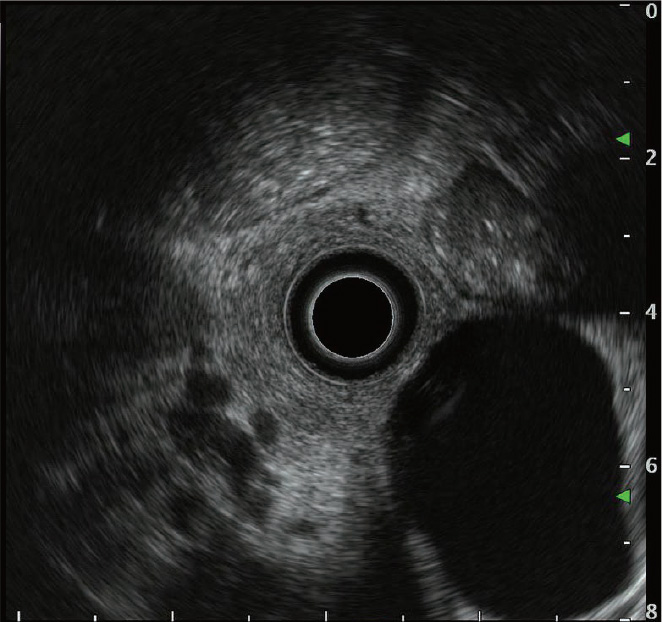

ラジアル走査式EUSは、360度の超音波画像を得られる反面、目的とする対象物が視野の辺縁に位置し観察しにくいことがあります(図a)。その場合には、スクロール機能を利用し、画面中央に対象物を移動させ観察しやすくします(図b)。また、胆膵疾患の病変は小さいことが多く、あらかじめ設定された表示レンジでは病変が小さく描出される場合があります。表示レンジは、超音波画像のサイズを変更することが可能であり、対象物が小さい場合に有用です(図c)。

図a

図b

図c